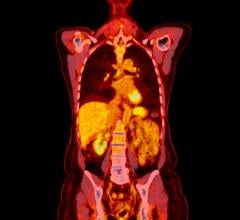

June 18, 2024 — Positron Corporation, a leading molecular imaging medical device company offering PET and PET-CT ...

June 14, 2024 — Positron Corporation, a leading molecular imaging medical device company offering PET and PET-CT ...

June 13, 2024 — The Society of Nuclear Medicine and Molecular Imaging (SNMMI) hosted more than 8,000 physicians ...

June 13, 2024 — Positron Corporation, a leading molecular imaging medical device company offering PET and PET-CT ...